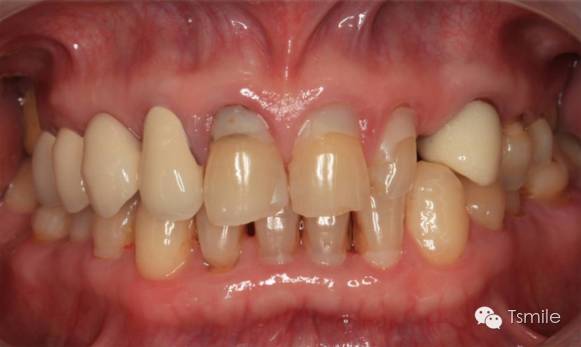

牙列重度磨耗的患者,特別是全牙列重度磨耗的患者,其口腔美觀和功能都受到了嚴(yán)重影響。患者不僅需要口腔美學(xué)重建,還需要口腔功能的重建。

例如面對一個牙列重度磨耗的美學(xué)修復(fù)患者,我們首先根據(jù)患者主訴和美學(xué)檢查形成美學(xué)設(shè)計,然后通過數(shù)碼圖像表達(dá)美學(xué)設(shè)計思想,制作診斷蠟型,口內(nèi)制作診斷飾面,更加真實地表達(dá)美學(xué)設(shè)計。根據(jù)患者的要求和口內(nèi)試戴情況調(diào)改診斷飾面,最終確定美學(xué)修復(fù)設(shè)計,即最終修復(fù)體的各種美學(xué)參數(shù)。接下來就是美學(xué)實現(xiàn)過程,在診斷飾面上進(jìn)行精確地牙體預(yù)備,制取印模和工作模型,技師按照最終診斷飾面的形態(tài)、大小和排列制作最終美學(xué)修復(fù)體,最后完成修復(fù)體粘接。